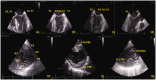

Mitral regurgitation is among the most common valvular heart diseases. Mitral regurgitation in patients with dilated cardiomyopathy is a complex pathology involving annular dilatation, papillary muscle displacement, systolic leaflet tethering, and left ventricular remodeling. Quantification of mitral apparatus damage in these patients is essential for successful interventional and surgical therapy. Mitral regurgitation in the presence of dilated cardiomyopathy is classified as Carpentier type IIIB, with restricted leaflet mobility as a standard feature. Echocardiography allows accurate evaluation of the complex anatomy and function of the mitral apparatus. Updated guidelines recommend two-dimensional followed by systematic three-dimensional echocardiographic evaluation in patients with mitral regurgitation. New three-dimensional echocardiographic software packages provide many parameters that help identify the precise morphology and function of the various components of the mitral apparatus, helping to determine the etiology of mitral regurgitation and evaluate disease severity. This review provides the first point-by-point approach to the assessment of all old and new echocardiographic methods, from the simplest to the most complex, used to examine the components of the mitral valve apparatus in patients with dilated cardiomyopathy. Although these parameters are still under research, this information will be helpful for establishing therapeutic procedures in a disease with a poor prognosis.